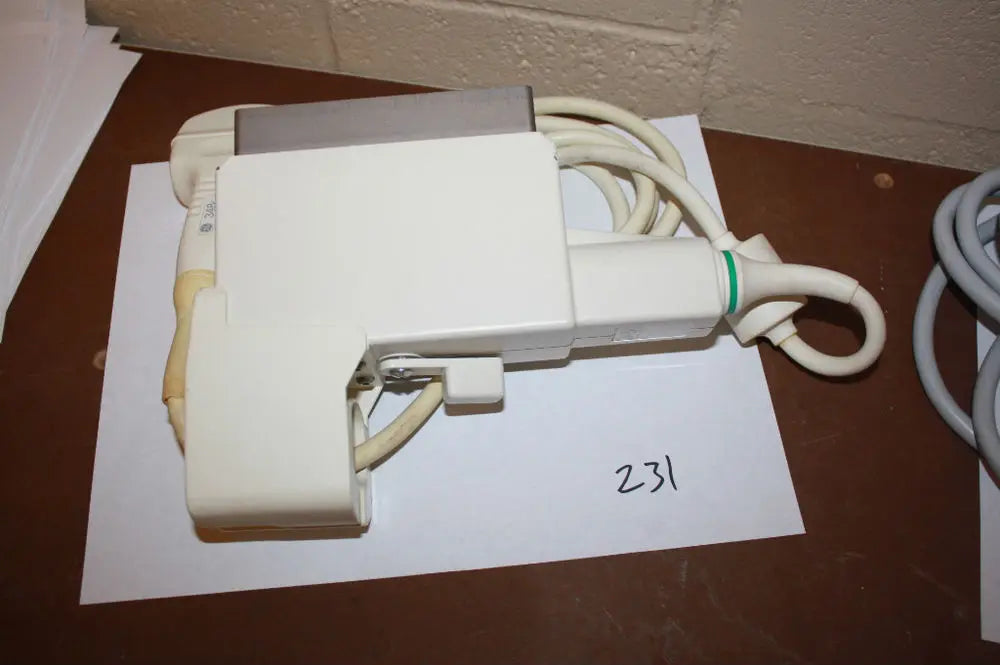

DIAGNOSTIC ULTRASOUND MACHINES FOR SALE

GE 348c Ultrasound convex ultrasound transducer

Sale price$ 1,439.90